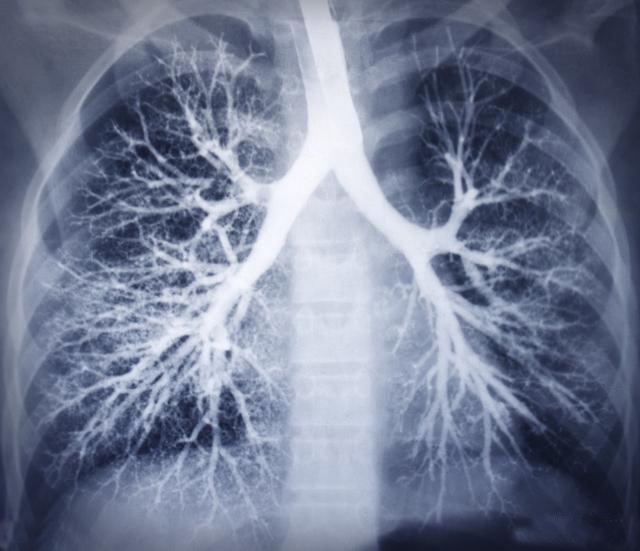

肺图片纹理

请教,为何右侧肺纹理不明显?

正常肺纹理(图片)

影像诊断中"肺纹理增多"该如何理解?

双肺纹理增多是什么意思

胸片--双肺纹理增多

肺纹理的分类

两肺纹理增多,模糊代表什么意思

再讲讲胸片里面的肺纹理增粗和斑片影

胸片中的"肺纹理增粗,肺纹理增重"是什么意思?严重吗?

影像诊断报告里的"肺纹理增多,紊乱"该如何理解?

余肺纹理增多,增粗,两肺门无明显增大,增浓;双膈面光整,肋膈角清晰

胸片示两肺门增大,两下肺纹理增多

肺纹理增粗到底是什么原因,为什么现代人动不动拍片就拍出这个病

肺纹理增粗可能是肺癌吗体检报告中纹理增粗代表什么要治疗吗